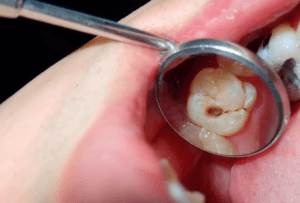

ما هو التهاب الأسنان؟

التهاب الأسنان او التهاب دواعم السن هو عدوى خطيرة تصيب أنسجة اللثة ويمكن أن تدمر الهياكل الداعمة للأسنان، بما في ذلك العظم السنخي. التهاب دواعم السن هو أحد الأسباب الرئيسية لفقدان الأسنان لدى البالغين ويمكن الوقاية منه تمامًا باتباع عادات صحية فموية مناسبة وزيارات منتظمة لطبيب الأسنان .

قد تشمل الأعراض الأخرى اللثة الحمراء أو المتورمة أو المؤلمة. ويحدث التهاب اللثة عادة بسبب البلاك، وهو عبارة عن طبقة لزجة من البكتيريا تتكون على أسطح الأسنان واللثة. وإذا لم تتم إزالة هذه البلاك اللزج بواسطة طبيب الأسنان، فقد تتصلب وتتحول إلى جير، مما قد يؤدي إلى تهيج اللثة، مما يؤدي إلى النزيف.

وإذا لم يتم علاج التهاب اللثة، فقد يؤدي التهاب اللثة إلى التهاب دواعم السن، وهو شكل أكثر شدة من أمراض اللثة المعروفة باسم التهاب دواعم السن أو ” التهاب الاسنان “.

عندما لا يتم علاج التهاب اللثة، تتراكم البلاك وتنتشر تحت خط اللثة. تطلق البكتيريا الموجودة في البلاك سمومًا تهيج اللثة وتؤدي إلى التهابها. يؤدي هذا إلى تحفيز استجابة الجسم للإلتهابات الموجودة، مما يؤدي إلى إتلاف العظام وأنسجة اللثة التي تثبت الأسنان في مكانها، مما يؤدي إلى التهاب دواعم السن.